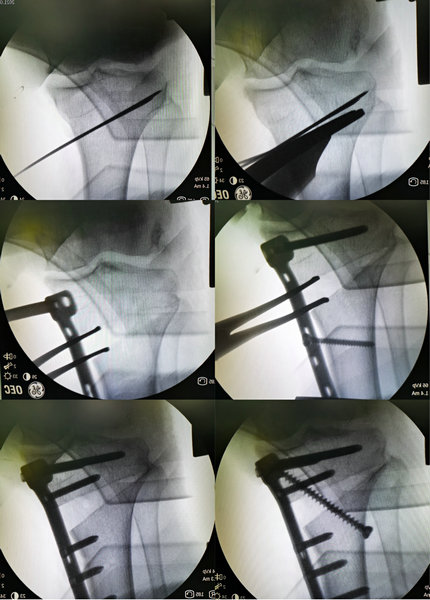

经全面研究后,针对王阿姨的病情、结合王阿姨年龄、膝关节活动度差等因素。刘主任带领骨外科四病区团队经过详细的术前检查和多次讨论,最终决定采用胫骨高位截骨矫形(HTO)辅以关节镜微创技术,为王阿姨治疗膝关节骨性关节炎。刘洋主任与患者及家属进行了充分沟通后,同意以上术式的治疗方式。手术过程十分顺利,术后王阿姨很快就恢复了,畸形及下肢力线等问题也得到了明显的改善,更主要是的是,一直困扰她的膝关节疼痛问题也终于得到了解决,王阿姨很开心,对手术效果非常满意。(供稿、摄像:骨外科四病区 王彪 编辑:宣传科 张宁)

术中影像

HTO手术全称为胫骨高位截骨术,是一种保膝手术,是目前公认的治疗膝关节内侧间室骨性关节炎并内翻畸形的安全有效方法。其手术原理如下:通过在胫骨内侧适当的切锯与撑开骨缺口、人工骨填充与骨板骨钉固定,藉以矫正膝关节内翻的生物力学轴线。由于可以减低内侧股骨髁与胫骨平台关节面的压力,藉以提供膝关节内侧磨损软骨修复再生的环境,减轻内侧间室的疼痛。对于主要膝关节疼痛为内侧关节面软骨所引起者,是很好的治疗手段。